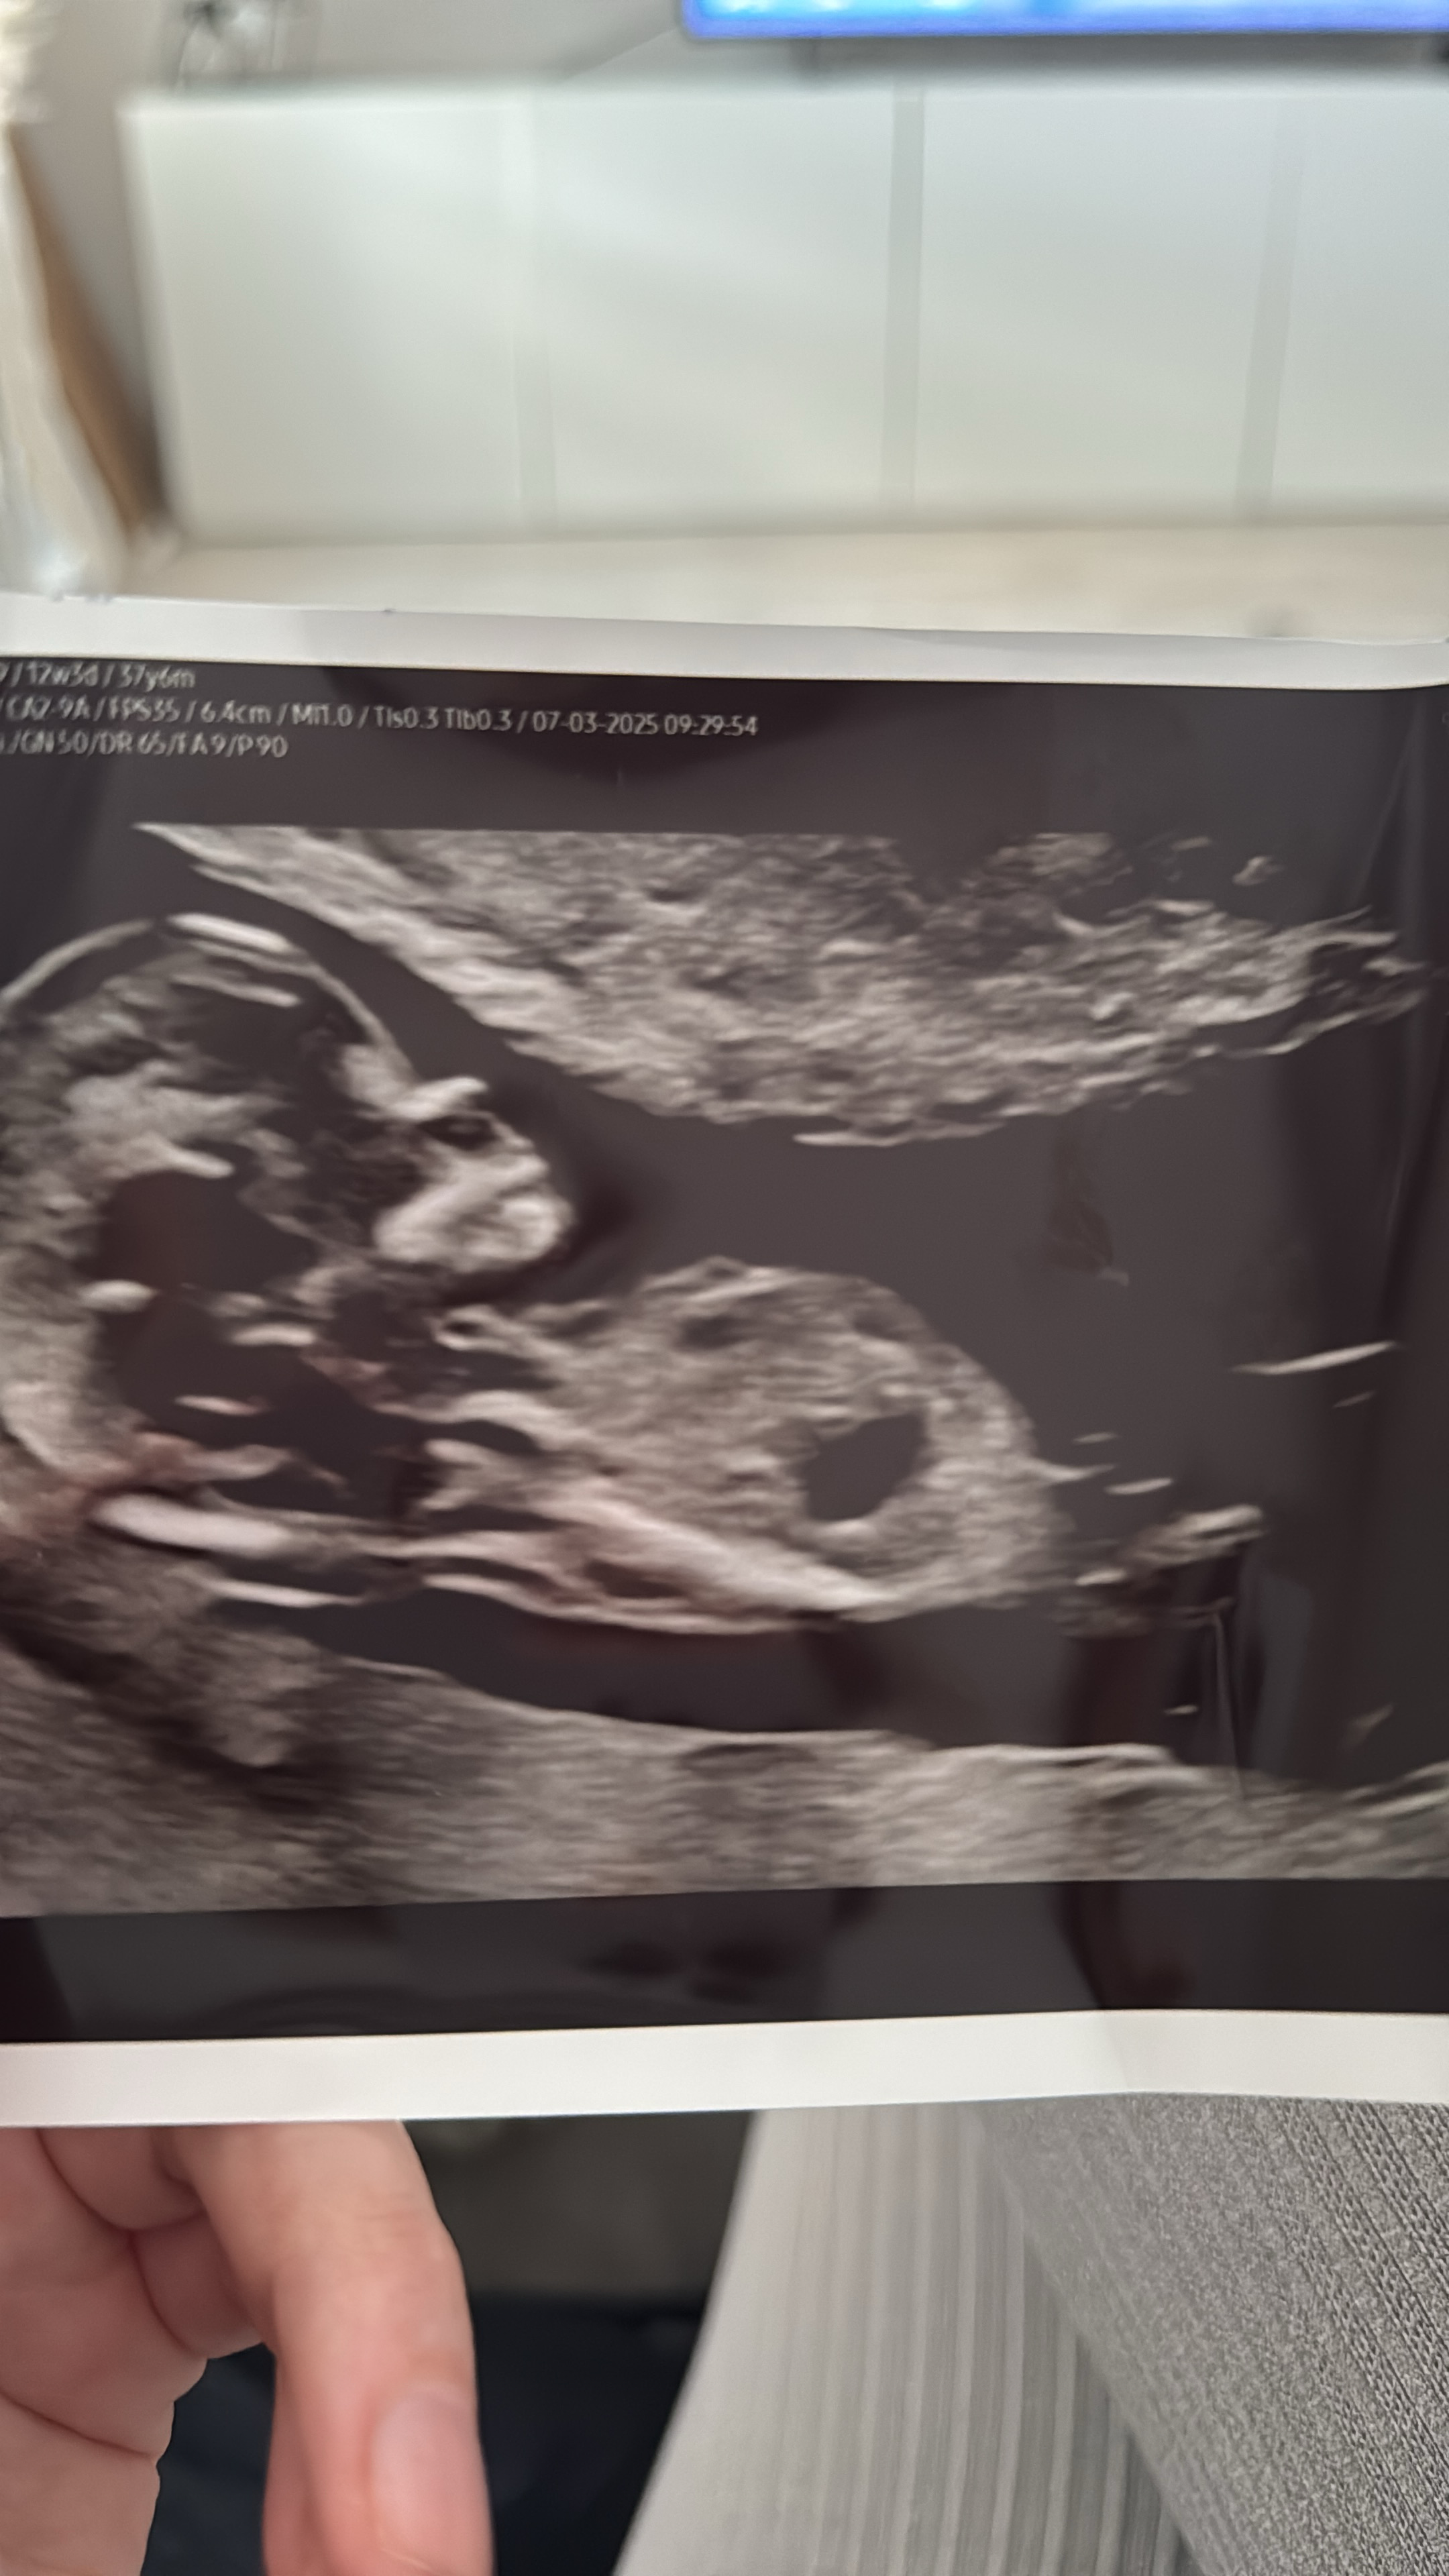

Ei näy nubia. Vain napanuoran alkupää näyttäisi olevan toi pätkä tossaHaluaako joku yrittää analysoida meidän bebeä? Ultran aikaan viikkoja on ollut 12+6.

Oon yrittänyt lukea nubista ja katsella erilaisia kuvia mut en nyt edelleenkään tiedä mitä kohtaa tässä pitäisi tuijotellaoltiin analysoivinamme kovastikin häntä pojaksi ultrassa mutta myöhemmin kotona tajusin, että ollaan varmaan katteltu napanuoraa koko ajan…

Tässä en näe itse mitään. Tosiaan 12+1 osa on jo poikamaisia, mutta tyttölupaukset muuttuu vielä herkästi myös pojiksi.Hei viisaammat, kun tää tyyppi on tollee istuma-asennossa melkein, niin mikä tossa nyt sit vois olla kulma?Ultran mukaan raskaus 12+1, eli onko kaikki vielä tytön näkösiä tässäkohtaa?

Hei apua aivan, toihan on jalan luu?Tässä en näe itse mitään. Tosiaan 12+1 osa on jo poikamaisia, mutta tyttölupaukset muuttuu vielä herkästi myös pojiksi.